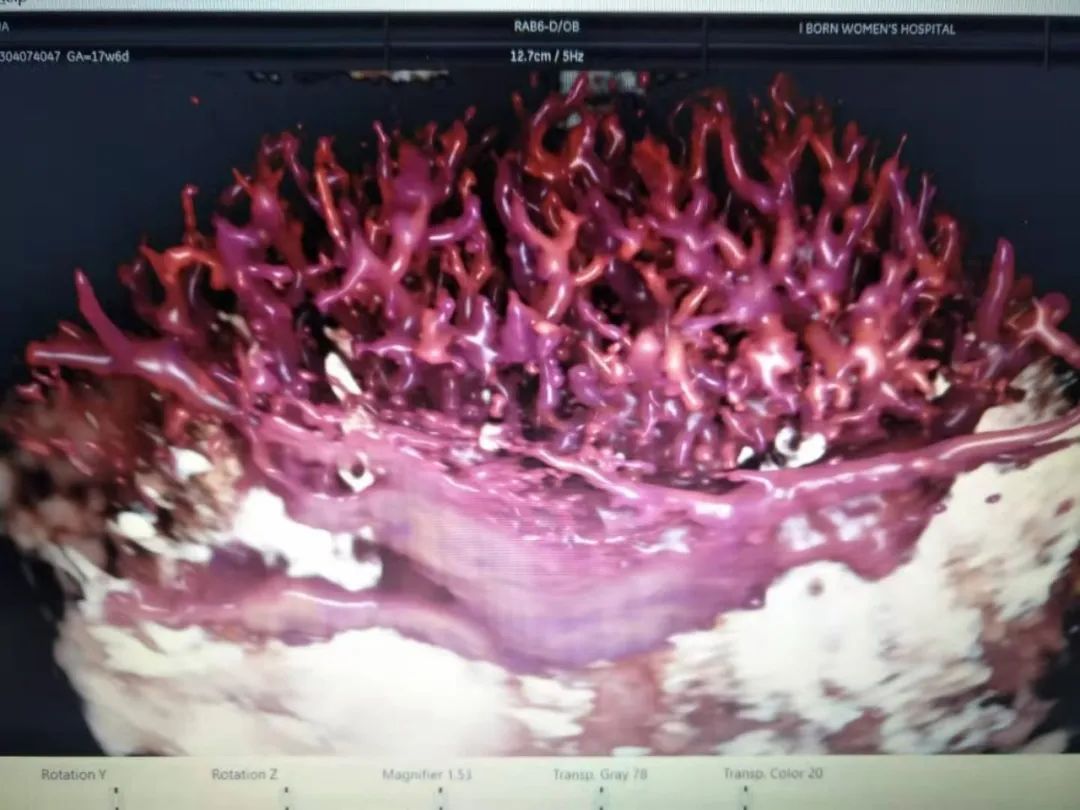

和平妇产医院引进的美国GE-E10四维彩超,提供更多、更科学的图像数据,实现胎儿影像的全方位动态演示,颠覆传统视觉理念,精准排畸不负众望!

/GE-E10四维彩超检查出的胎宝宝脐动脉迂曲/